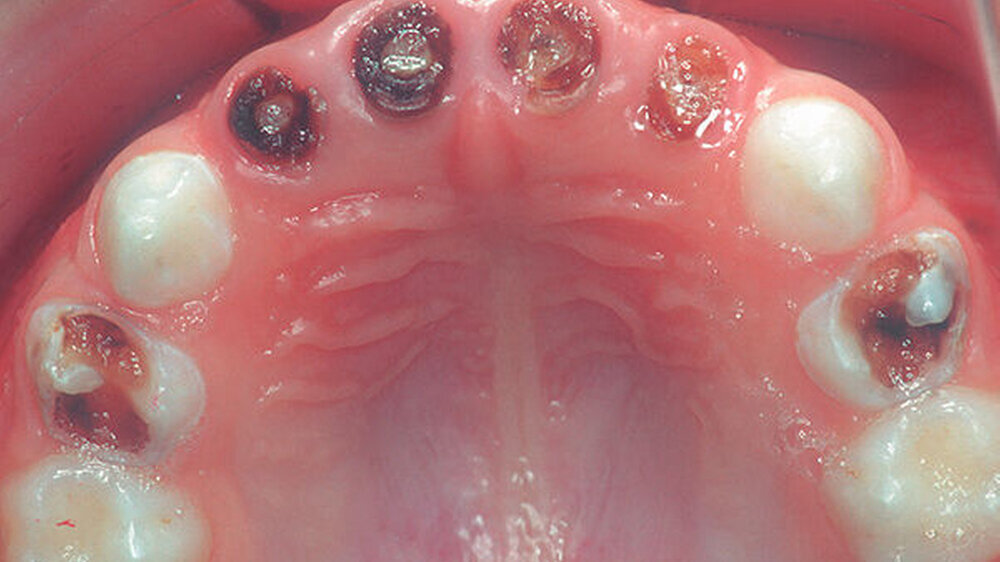

ThemenseiteEarly Childhood Caries (ECC)dentimagesZahnärztliche Mitteilungen 01.09.2021 PraxisZahnärztliche Mitteilungen Zur Übersicht